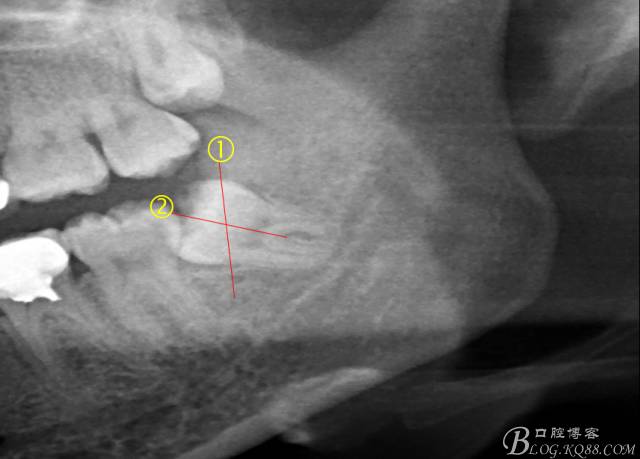

檢查:(1)37牙合面齲,卡探針.         (2)38近中埋伏阻生

X全景片示38近中三類阻生,非融合根,近中根壓下頜管,37遠中鄰面中齲樣影像。

先分析智齒的情況,口內(nèi)直觀是半個牙尖都沒露出來,差一點就完全埋伏了。磨牙后墊的可操作面積中規(guī)中紀,X全景片示三類阻生,根冠比例是1:1,非融合根,近中根壓下頜管。

術(shù)前分析:智齒分牙的方法不少,但個人感覺都與這十字分牙法差不多,大多數(shù)阻生齒的分牙都在此基礎(chǔ)上進行改進。